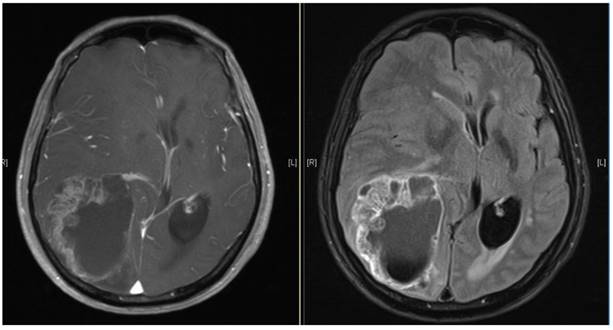

Figure 1

Brain MRI images of a patient diagnosed with ESCC who experienced brain metastasis 22 months after surgical resection of the esophagus. The maximal brain lesion diameter was 6.8 cm. The patient underwent surgery followed by local irradiation of the lesion and survived for 34 months after diagnosis of brain metastases.